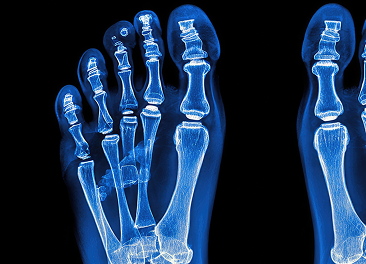

Digital X-Ray

High-resolution radiographic imaging used to evaluate fractures, joint alignment, degenerative changes, and structural abnormalities within the foot and ankle.